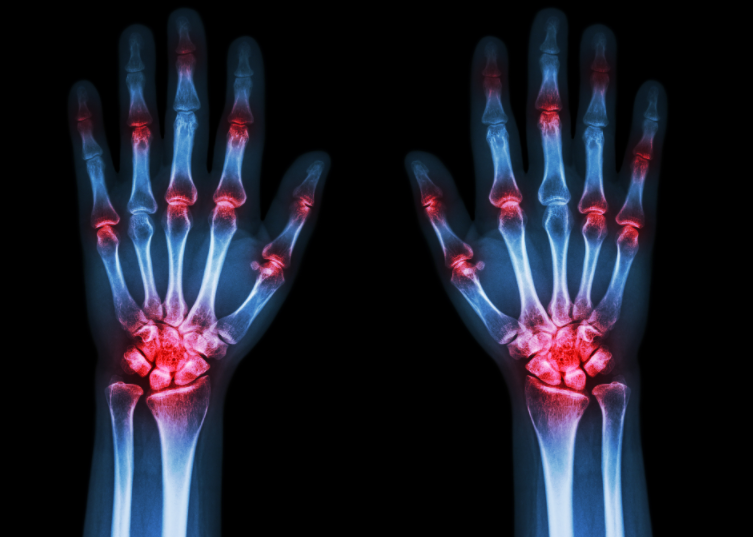

医生也是直言,以往,大家总觉得痛风是中老年人才会得的病,但随着饮食结构和生活方式的改变,该病正愈发年轻化。

这并非个例。相关研究发现,在我国的高尿酸及痛风患者中,18-35岁人群占比高达60%。而在儿童群体中,高尿酸的蔓延速度同样惊人——近年来,儿科门诊的高尿酸患儿数量逐年攀升,甚至有医院统计,10岁以下的“小胖墩”中,高尿酸发生率已达15%以上。看到这些数据,很多家长满心疑惑:孩子既不喝酒,也没天天大鱼大肉,尿酸怎么会这么高?难道是平时“补”错了?其实,让孩子尿酸飙升的真正“隐形杀手”,不是肉,而是我们常常忽视的——糖,尤其是添加糖和果糖。